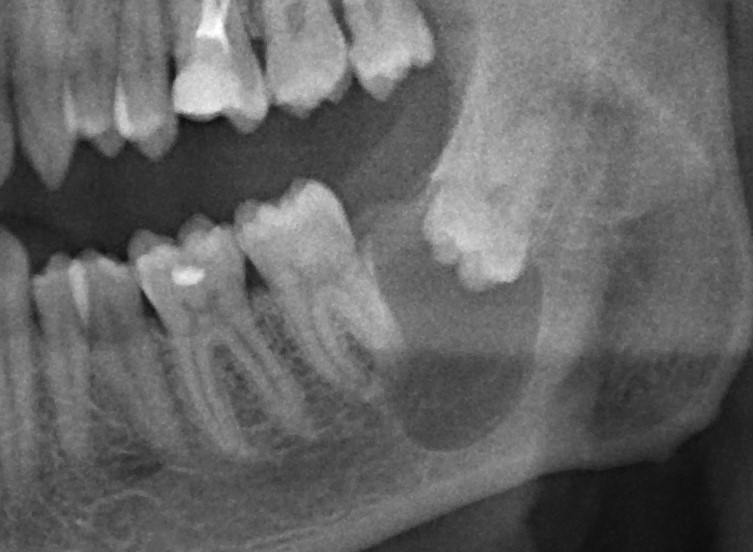

Обязательным обследованием для планирования операции синуслифтинга является компьютерная томография (КЛКТ). В верхнечелюстной пазухе могут быть перегородки и карманы, на обычном панорамном снимке увидеть их сложно. Также КЛКТ даёт возможность измерить расстояние АБ (с этого мы с вами начинали статью):